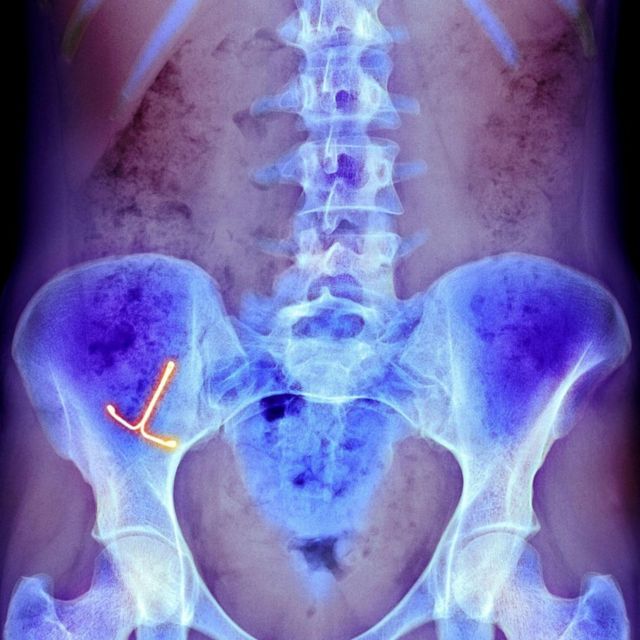

கருத்தடை சாதனங்களால் அபாயம்

மருத்துவ காரணங்களுக்காகவோ அல்லது பிற காரணங்களுக்காகவோ பிறப்புறுப்புக்குள் சில சாதனங்கள் செலுத்தப்படுகின்றன.

அதாவது, கருப்பையினை நிலைகுலையாமல் தாங்க செய்யும் பெசரிகள் (Pessaries) அல்லது கருத்தடை சாதனங்கள் உள்ளிட்டவற்றை குறிப்பிடலாம். அவை தம் உடலில் செலுத்தப்பட்டிருப்பதை நோயாளி மறந்துவிட்டிருக்கலாம் அல்லது அவை உடலுக்குள்ளேயே சேதமடைவதை உணராமல் இருக்கலாம்.

இவை நோய்த்தொற்றுகள், ஃபிஸ்துலாக்கள் (உடலில் இரண்டு உறுப்புகள் அல்லது துவாரங்களை இணைக்கும் அசாதாரண பகுதி) மற்றும் கல் உருவாக்கம் போன்ற நீண்ட கால அபாயங்களை ஏற்படுத்துகின்றன.